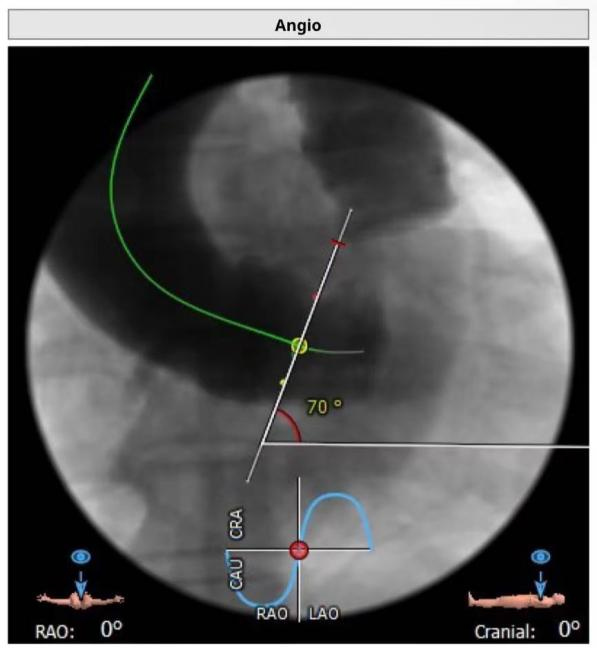

4 心脏角度 约68°,呈横位+升主扩张

患者为三叶瓣,瓣叶增厚,极重度钙化,左冠窦可见柱状钙化延申至流出道,双冠脉风险高度尚可,瓣叶未见冗长,考虑冠脉风险较低,心脏角度约68°,呈横位+升主扩张,预备上Snare;收缩期左室测值较小且流出道短径约16.8mm,选择20球囊预扩,预装L26 Venus-A瓣膜。

1、术前CT评估重要,对瓣膜结构及外周入路需充分评估,主动脉夹角>50°时要预估手术跨瓣困难;若合并升主动脉扩张,通常会进一步增加跨瓣难度,本例患者主动脉夹角68°,同时伴有升主动脉扩张,导致导丝跨瓣后继操作困难;